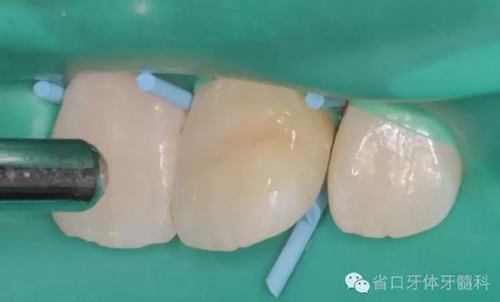

斷冠粘接前試對(duì)接

DUO-LINK樹脂水門?。˙ISCO)對(duì)位粘接,(牙齦紅腫,沒有安放橡皮障)

光固化,去除多余樹脂水門汀,近中鄰面洞和舌側(cè)開髓孔樹脂充填,拋光,調(diào)整咬合。